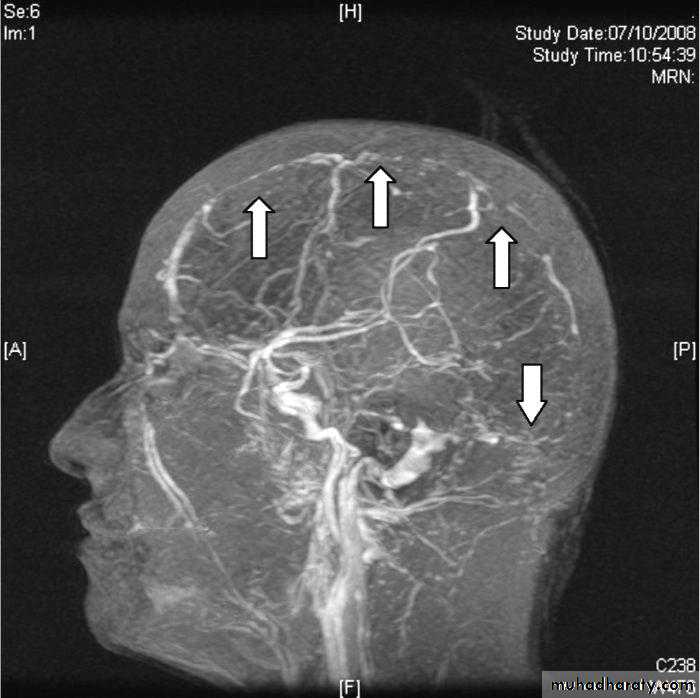

CT angiograph or MRA (magnetic resonance angiography) in case of AVM (arteriovenous malformation) suspension.

Four-vessel cerebral arteriography, CT angiography and magnetic resonance angiography may be used to detect aneurysm and AVM.

MR venography demonstrates a filling defect in the affected vessel.